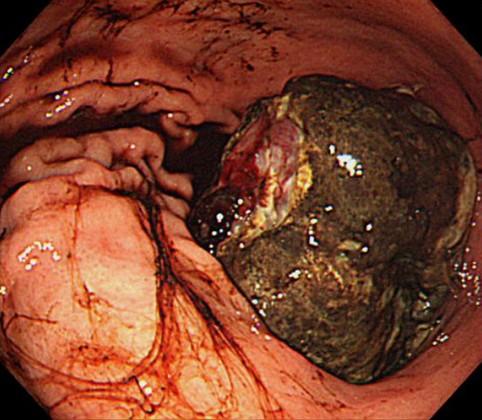

症例提示(所在地,施設名等): 福岡県・ 九州医療センター (平賀聖久先生、渡辺一平先生、村中光先生からの提供症例)

政策ネットワーク症例 ,GI症例研究会

症例登録日 2011/06/01

画像数 19

性別 男性

年齢 70-74

画像ID:11714

疾患(病理主体)の分類悪性非上皮性腫瘍/その他

部位(臓器別)胃(部位)/2つ以上

検査方法内視鏡

腫瘍の肉眼分類1型(腫瘤型)/

病変の最大径(ミリ)40以上

腫瘍の深達度mp

多発腫瘍(同一臓器)

多重腫瘍(他臓器)